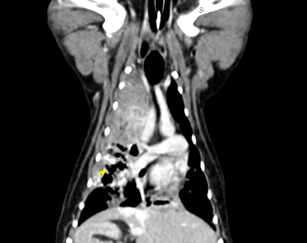

狗狗 肺臟腫瘤 Pulmonary carcinoma

持續數月的咳喘 他院懷疑心臟問題轉診來築心,經由電腦斷層掃描及胸腔採樣

確診為惡性腫瘤,由於腫瘤已經擴散不適合外科手術,主人最後決定使用化療延長壽命